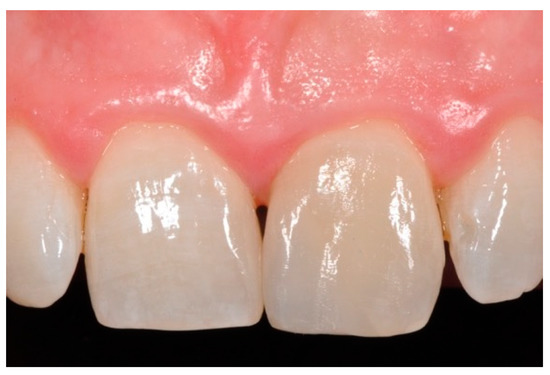

Finishing and polishing procedures were performed with a diamond bur (WL 268 014 Horico, Berlin, Germany), silicone points (Identoflex, Kerr, Bioggio, Switzerland) brushes (Jiffy Goat Air Brushes, Ultradent Products, South Jordan, UT, USA), and diamond pastes (Diamond Polish Mint, Ultradent Products, South Jordan, UT, USA) (Figure 13 and Figure 14). Satisfactory clinical and radiographic outcome was considered satisfactory at 3-months, 1-year, and 5-years post-operative (Figure 15, Figure 16, Figure 17, Figure 18 and Figure 19).

Figure 18.

Five years post-operative.